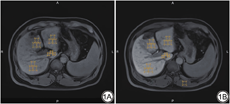

由两名具有多年腹部磁共振成像经验,且对患者的临床、实验室信息不知情的放射科医师对图像进行感兴趣区(ROI)选取,将二者测量结果取均值并进行记录,具体方法如下:使用工作站(eFilm workstation)分别在增强前和增强后20 min肝胆期(hepatobiliary phase,HBP)图像上绘制感兴趣区并测量信号强度(signal intensity,SI)。分别在肝右叶、肝左内叶、肝左外叶、肝尾状叶画取3个ROI,肝右叶、肝左内叶、肝左外叶的ROI面积为120~180 mm2,肝尾状叶ROI面积为20~30 mm2,画取时要避开局灶性病变、血管和胆管以及成像伪影,连续选取三个层面,每个层面的ROI大小和位置要尽量相同,每个肝叶共画取九个ROI,取平均值得到各个肝叶的增强前信号强度(SIpre)和肝胆期信号强度(SIHBP)。随后在相应层面的竖脊肌上分别画取一个ROI,面积为120~150 mm2,取平均值得到竖脊肌信号强度(SI肌肉),见图1。LRE由肝胆期和增强前肝实质信号强度的差值除以增强前肝实质信号强度,LMR由肝胆期的肝实质信号强度除以竖脊肌信号强度,计算公式如下。